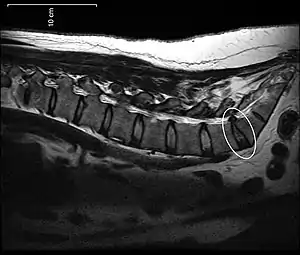

Протру́зия межпозвонкового диска — патологический процесс в позвоночнике, при котором межпозвонковый диск выбухает в позвоночный канал без разрыва фиброзного кольца (вариант грыжи диска). Чаще всего локализуется в поясничном и реже — шейном отделах. В клинической практике встречается гораздо чаще, чем экструзия.

При протрузии межпозвонкового диска фиброзное кольцо сохраняет целостность, и сдавливание (раздражение) корешков носит интермиттирующий (периодический) характер. Размер выбухания в различных случаях составляет от 1 до 5 мм.